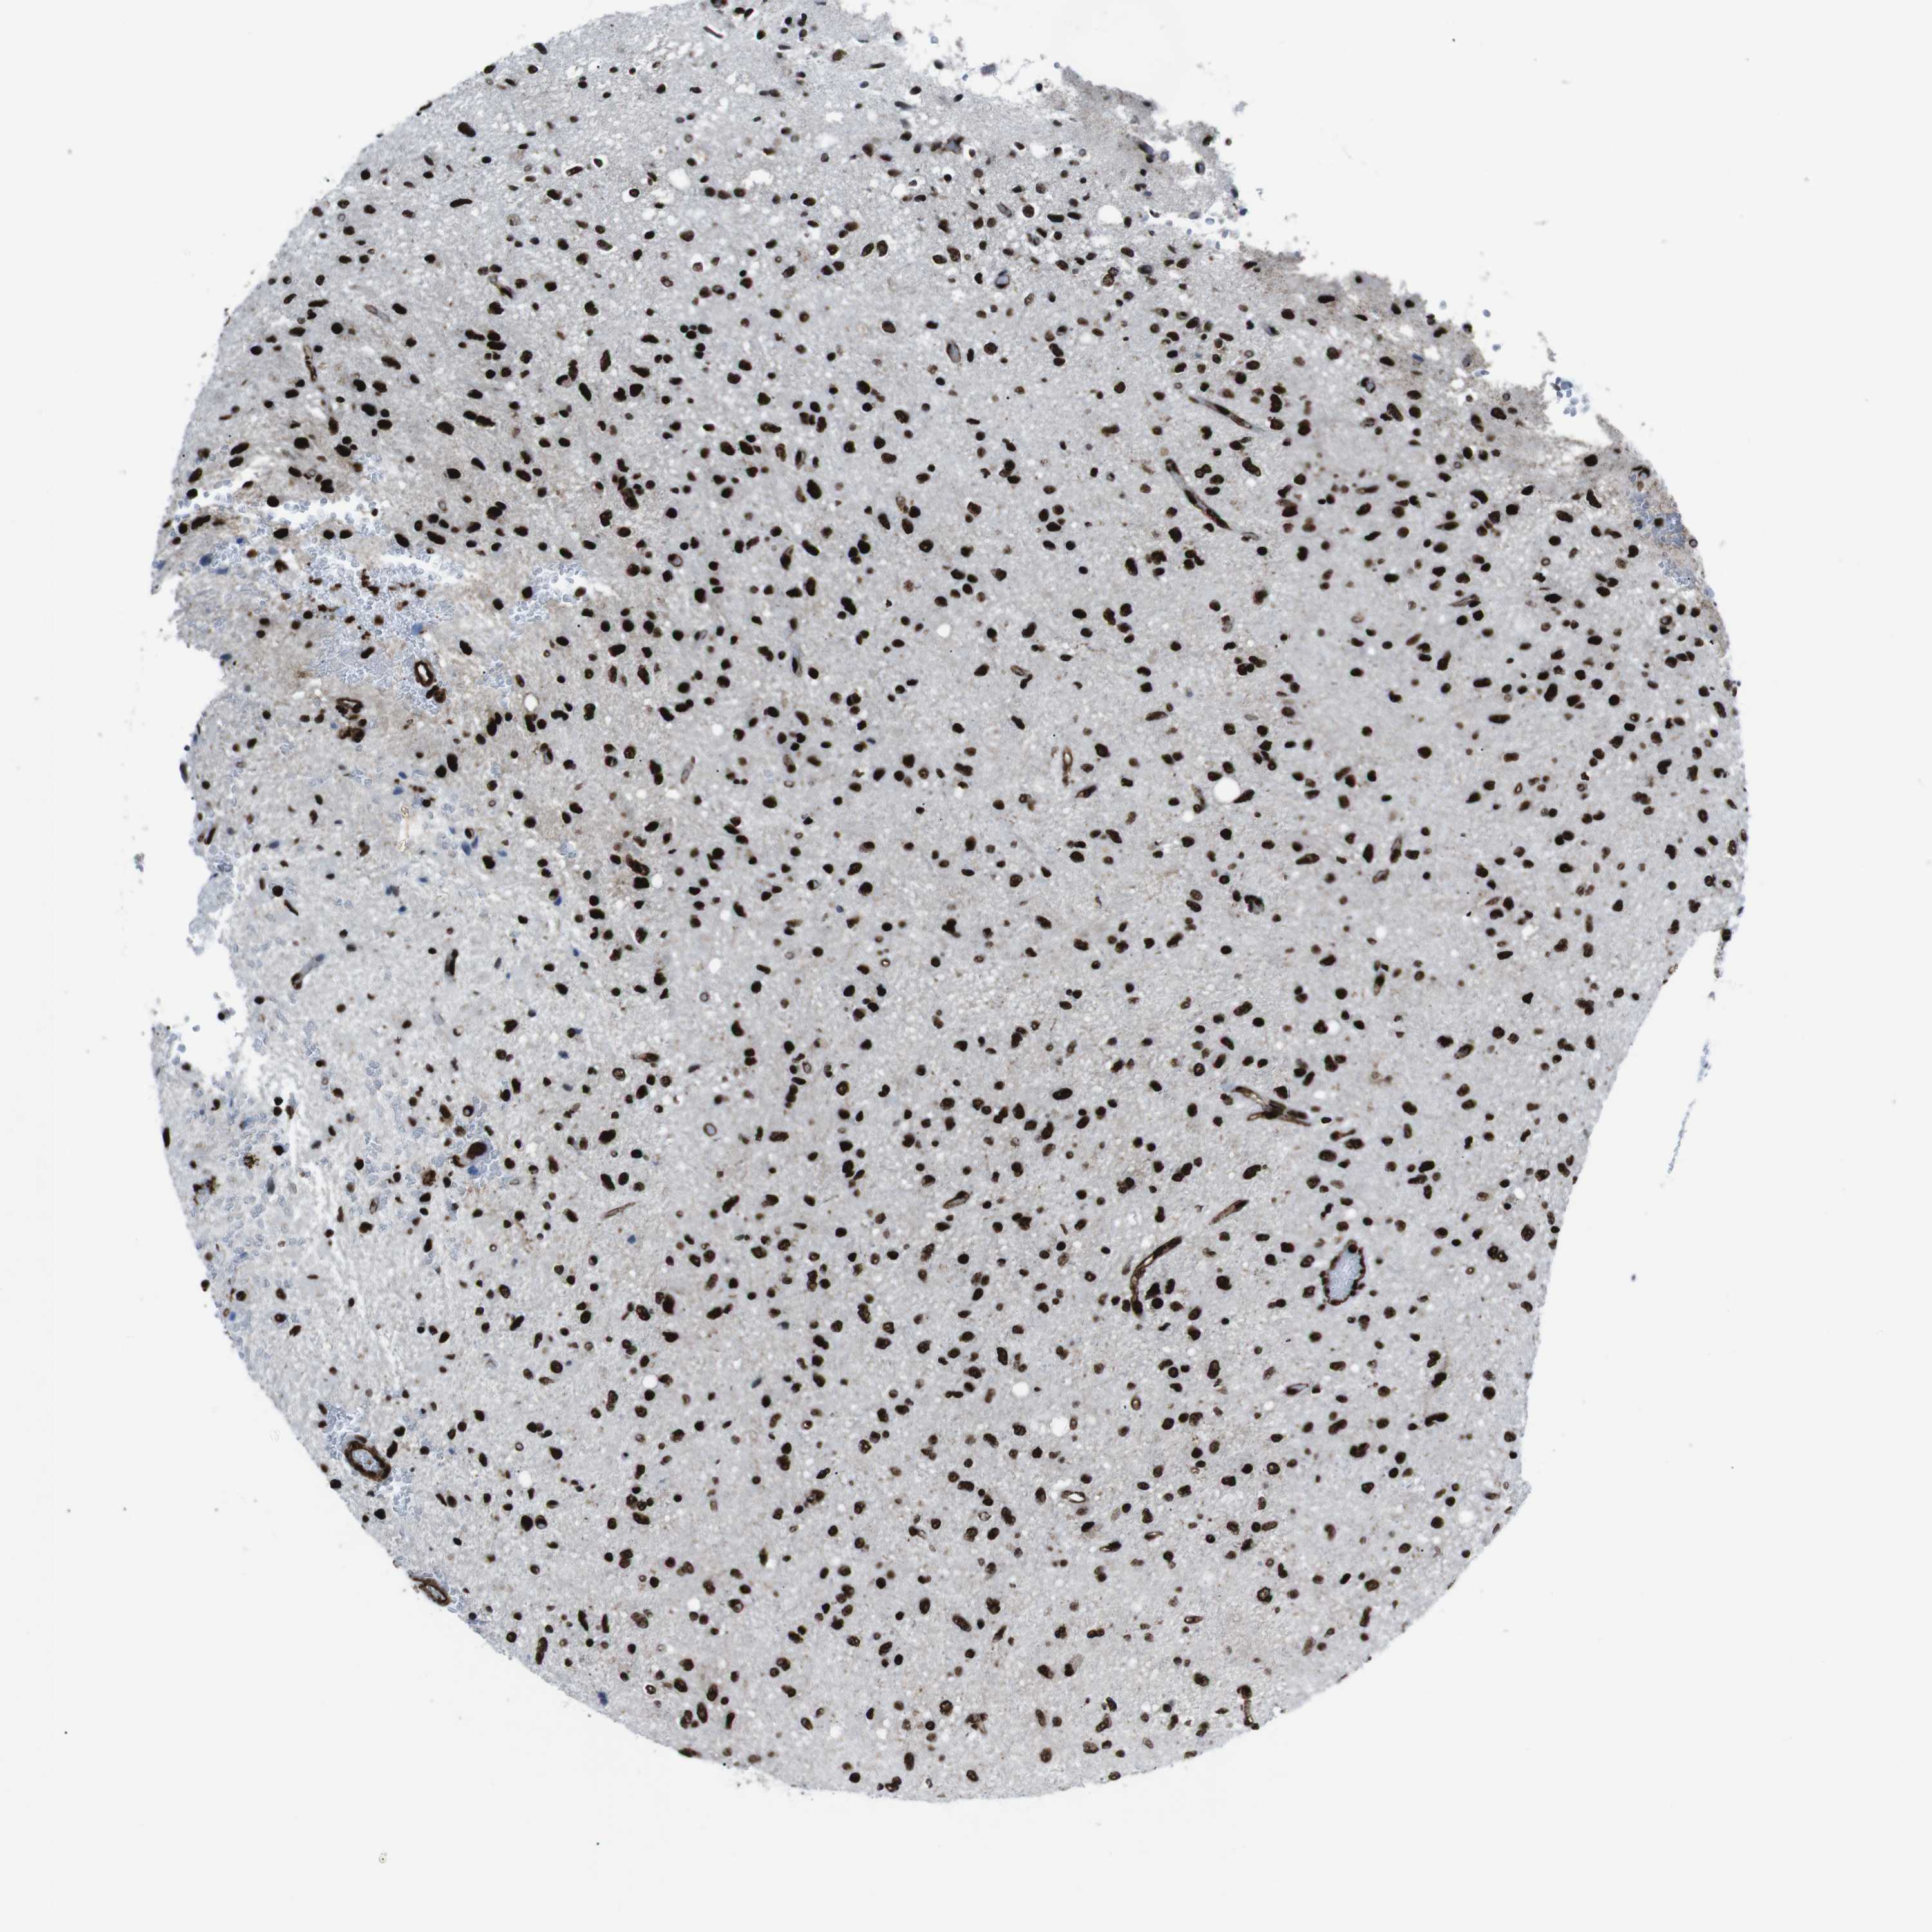

GLIOMA - Protein expressioni

A mouse-over function shows sample information and annotation data. Click on an image to view it in a full screen mode. Samples can be filtered based on level of antibody staining by selecting one or several of the following categories: high, medium, low and not detected. The assay and annotation is described here.

Note that samples used for immunohistochemistry by the Human Protein Atlas do not correspond to samples in the TCGA dataset.

Antibody stainingi

Antibody staining in the annotated cell types in the current human tissue is reported as not detected, low, medium, or high, based on conventional immunohistochemistry profiling in selected tissues. This score is based on the combination of the staining intensity and fraction of stained cells.

Each image is clickable and will lead to virtual microscopy that enables deeper exploration of all samples and also displays staining intensity scores, fraction scores and subcellular localization as well as patient and tissue information for each sample.

Antibody HPA041057

Antibody HPA058707

Antibody CAB011532

Staining

High

Medium

Low

Not detected

Intensity

Strong

Moderate

Weak

Negative

Quantity

>75%

75%-25%

<25%

None

Location

Nuclear

Cytoplasmic/membranous

Cytoplasmic/membranous,nuclear

Glioma, malignant, High grade